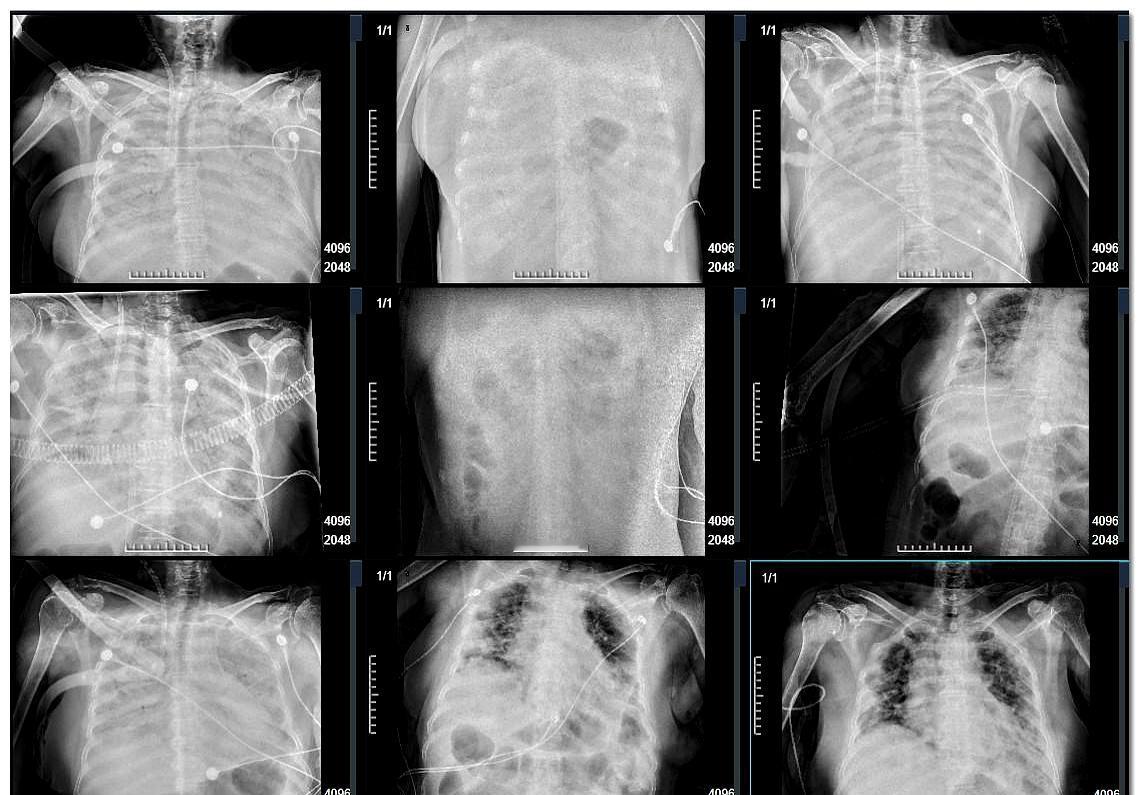

肺结节到肺癌经历的4个阶段。

肺部结节若为肺癌,会有这些“危险变化”在临床诊疗中,肺部结节是呼吸科常见的“信

肺癌结节只有8mm就转移到了胸膜失去了根治机会,虽然很少见,但的确存在结节长在